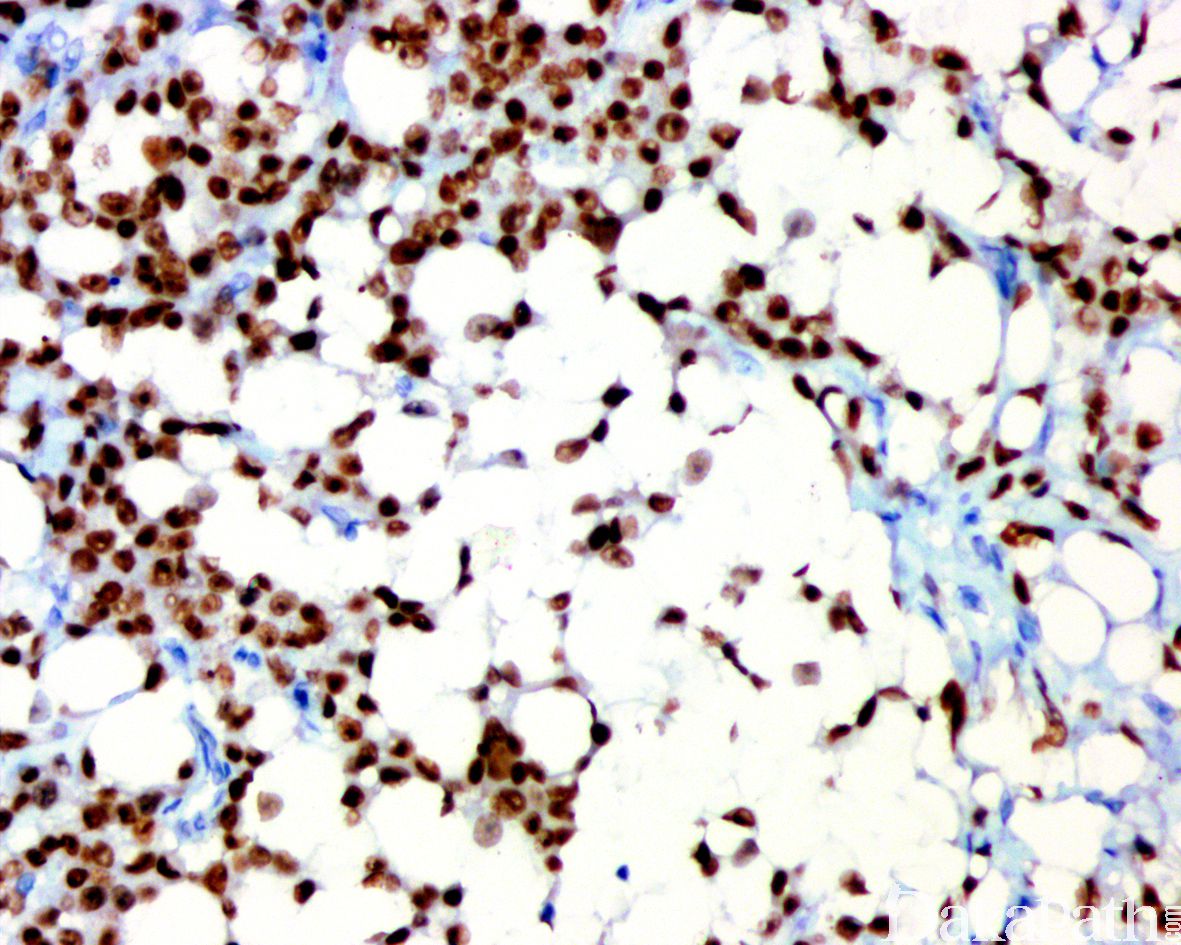

浸润性尿路上皮癌,富脂质

Infiltrating urothelial carcinoma, Lipid-rich

尿路上皮癌瘤细胞胞浆内存在多个空泡挤压核形成类似于脂肪母细胞的瘤细胞

特征性形态学改变是存在大的脂肪母细胞样细胞,具有 1 个或多个胞浆空泡,挤压细胞核;

表达 AE1/3,P63,CK7, thrombomodulin, EMA,Cam5.2,CK20 和 GATA3,Vimentin 和 S100 阴性,黏液染色阴性。